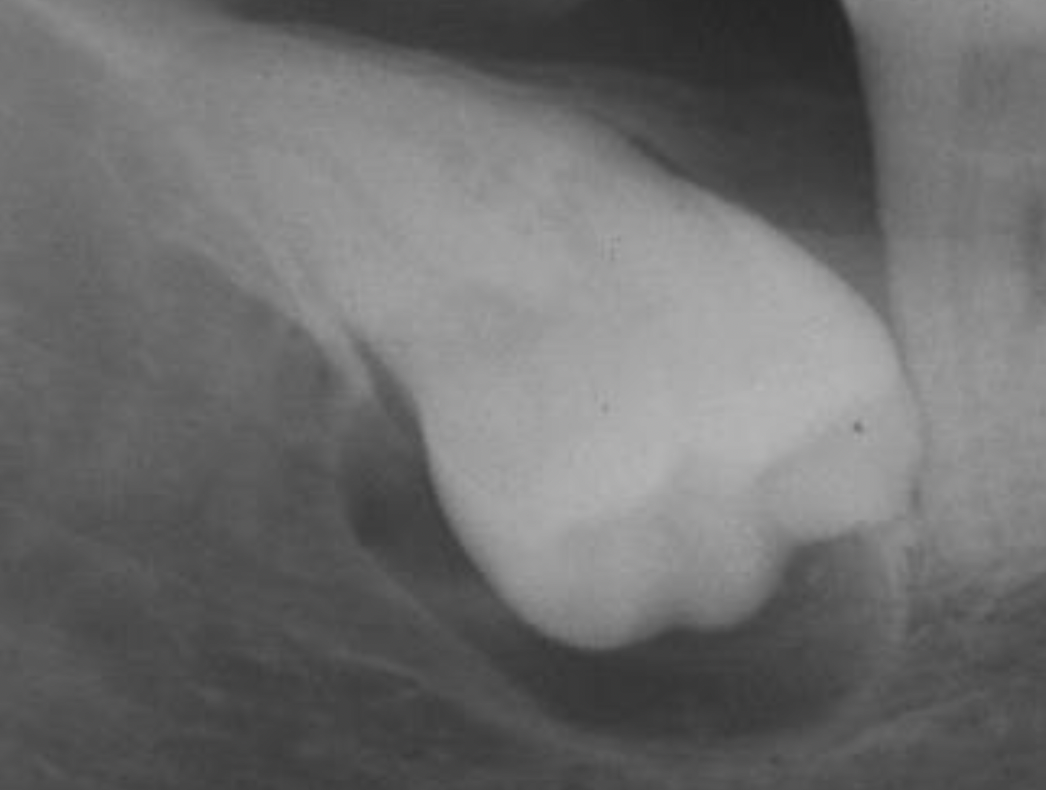

26

ameloblastic fibroma

27

28

29